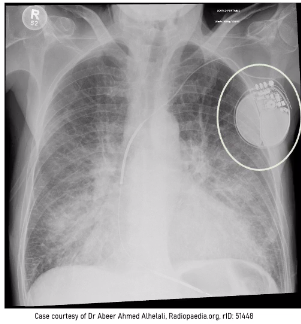

whats this?

cardiopacemaker